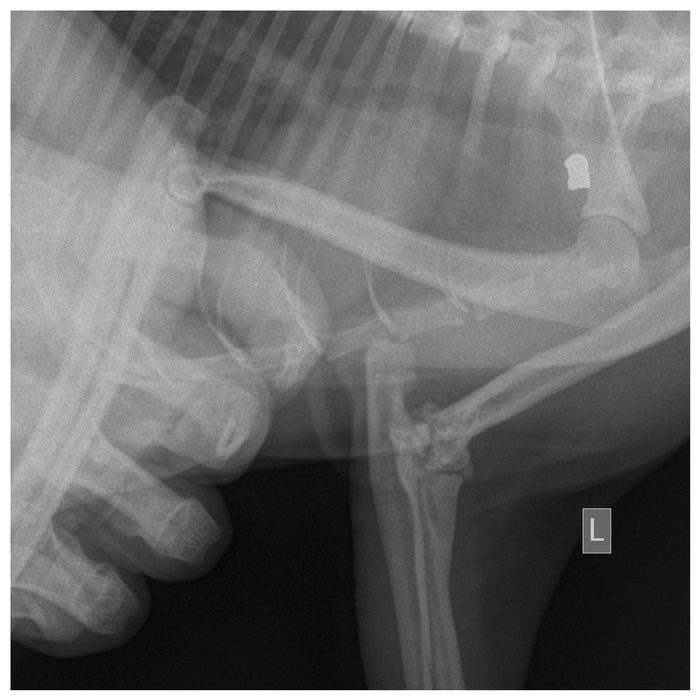

Нужна помощь коту

Привет. Такая история. Мы шли по городу и увидели уличного кота, который залез под стоявшую на обочине

машину. Она могла поехать в любой момент и мы решили приманить его кормом. Кот вышел и мы увидели как

он ужасно хромает на переднюю лапу. Она была неестественно выгнута, он сильно хромал и было видно что

это приносит ему страдания. Мы решили что это закрытый перелом и я бегом побежал за переноской чтобы

транспортировать его в ветклинику. Придя в ветклинику мы сделали рентген лапы и оказалось что это

вывих локтевого сустава вызванный ВНИМАНИЕ!!! ПУЛЕЙ.

Да, пуля от пневматического оружия. У меня нет слов чтобы описать тех, кто смог выстрелить

в беззащитное животное, которое по своей простоте не ждало чего то плохого. Вывих не так страшен как

перелом, но в нашем случае оказалось что это застаревшая травма. Это произошло не менее года назад.

Коту требуется операция. Да, это не смертельно, он сможет жить и адаптироваться, но представьте себя,

что вам до конца жизни придется жить с коленом выгибающимся назад. Это страдания, на которые обречен

добрый и ласковый кот, который ни кому не сделал зла. Мы не можем оставить его у себя, потому что уже

приютили кота и кошку. Он живет на улице, у соседнего дома. Остается только кормить и наблюдать за ним.

Теперь немного о цифрах. Опрация стоит в районе 6000 рублей, и передержка на время реабилитации еще

около 3000р. Итого 9000 рублей. Я надеюсь что есть неравнодушные люди. Даже 100 рублей могут внести вклад.

Это съеденый бургер или пачка сигарет, без которых можно прожить. Я надеюсь вместе мы сможем собрать эту сумму.

Все чеки, фото и видео отчет я готов предоставить. Кот пострадал от рук человека, и человек обязан ему

помочь. Я никого ни к чему не принуждаю, но если вы вдруг захотите внести вклад в доброе дело я оставлю внизу

реквизиты. Спасибо. Будьте добрее к животным.